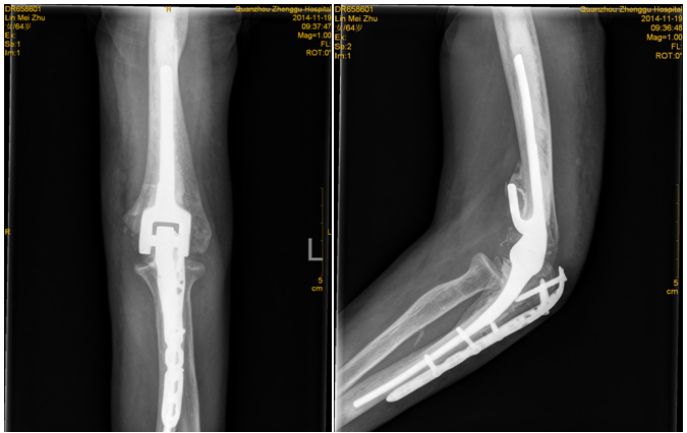

4.关节置换术

老年人关节内骨折合并骨质疏松症时,软骨下骨质量差,骨折块易嵌入关节面,解剖复位困难,骨折复位在下地负重或关节活动时难以维持,因此内固定治疗效果不佳。此时可酌情选择关节置换治疗,能够获得更好的预后。当骨折未累及关节面,但存在股骨头缺血性坏死风险时,例如股骨头下骨折或肱骨近端骨折,关节置换术的疗效优于内固定[27][28][29]。随着反肩关节置换术的出现,越来越多的骨科医生选择关节置换术治疗复杂的肱骨近端骨折,获得了良好的治疗效果;而肘关节置换术已经成为复杂骨质疏松性肱骨远端骨折的常规治疗手段,临床研究也验证了其优良且可靠的治疗效果[28]。因此,当骨质疏松性骨折骨质量差,骨折碎片较小时,人工关节置换术应首先考虑。